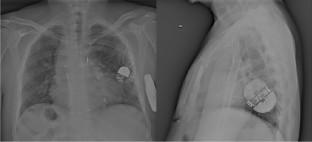

Results: From a large cohort of 345 patients enrolled in the S-ICD Monaldi care registry, which encompass all the patients implanted in the Monaldi Hospital of Naples, we considered 11 consecutive complex CHD patients (10M/1F aged 40.4 ±18.4 years) who underwent S-ICD implant after a previous PM implant, from February 2015 to October 2022. Mean follow-up was 25.5 ± 22 months. All the patients showed a good compliance to the device system with no complications (infections or skin erosions).

Conclusions: In complex CHD with already implanted PM devices, S-ICD implant appears to be a safe alternative to PM upgrading to transvenous ICD system, avoiding abandoned leads or life-threatening lead extraction. However, there are important issues with regard to testing and programming that need to be addressed at the time of implantation.